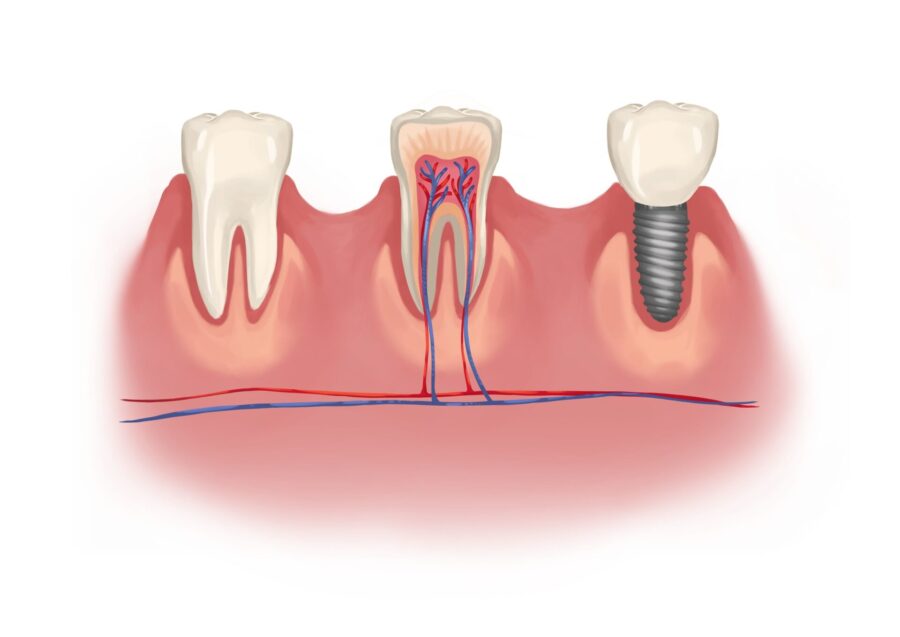

A traditional crown is placed over a natural tooth that’s still rooted in your jaw. It’s designed to restore and protect a tooth that’s been compromised — whether by decay, a crack, or wear over time.

This type of crown is supported by your natural tooth structure. After removing the damaged or weakened areas, the remaining tooth is reshaped so that a custom crown can fit securely over it. Once bonded in place, it restores strength, function, and appearance — often preventing the need for further treatment.

An implant crown replaces a tooth that’s already missing or can’t be saved. Instead of sitting on a natural tooth, it attaches to a dental implant — a small titanium post that’s placed in the jawbone to function like a tooth root.

- Traditional Crown: Sits on a reshaped natural tooth

- Implant Crown: Attached to a titanium implant post in the jawbone